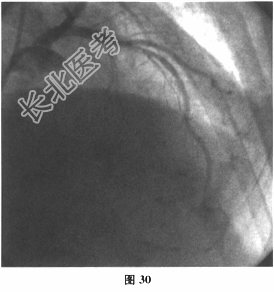

- 多项选择题4.[提示]心梗后第7天股动脉路径行CAG/PCI术,术中见mLAD90%狭窄伴钙化(图30), pRCA25%狭窄,mRCA50%狭窄, PDA50%狭窄。于mLAD处植入支架于mLAD病变处,残余狭窄25%, TIMI血流3级。手术结束后,返回病房上床时突然出现意识丧失, 呼之不应。